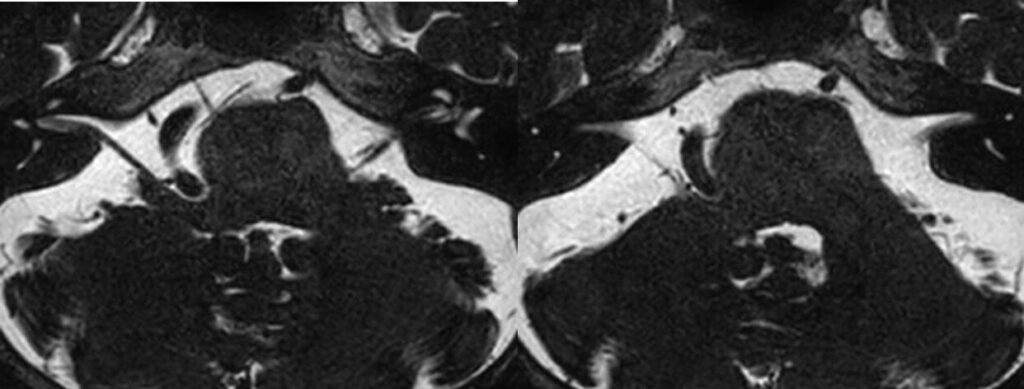

2603月 67歳男性の右顔面痙攣を手術しました。 2026 4/20 顔面痙攣・三叉神経痛 2026年3月22日2026年4月20日この患者さんもVA圧迫型でしたが、延髄誘発電位のM-TEPを併用しABR、ICGなど術中画像支援を駆使して手術を行いました。合併症なくうまく治癒できました。ScreenshotScreenshotScreenshotScreenshotScreenshotScreenshotScreenshotScreenshotScreenshotScreenshotScreenshotScreenshotScreenshotScreenshot 顔面痙攣・三叉神経痛 よかったらシェアしてね! URLをコピーしました! URLをコピーしました! 260306金 北海道神経セミナーで講演しました。 260313金 STROKE2026 1日目 この記事を書いた人 kikuta 関連記事 2603月 58歳女性の左顔面痙攣を治療しました。VAとAICAの複合型圧迫でしたがうまく治癒できました。 2026年3月21日 46歳男性、開眼できないほどのVA型左顔面痙攣を手術しました。術後まだ完全には消失していませんが痙攣は著明に軽減しました。 2026年3月3日 19歳女性の三叉神経痛を手術しました。術後痛みは消失した様子です。 2026年3月3日 87歳女性、繰り返しブロックを行いガンマナイフも行った、難治生三叉神経痛を手術しました。高齢ですが無事一発治癒しました。 2025年12月11日 左三叉神経痛の手術をしました。カルバマゼピンで抑えられい強い痛みがありましたが、手術後痛みが完全になくなり食事も取れるようになりました。 2025年12月5日 2025年8月 78歳 VA型の顔面痙攣の神経減圧術を行いました。M-TEPを併用し無事治癒しました 2025年12月4日 2025年5月 テグレトールで治らない左三叉神経痛の手術を行い直後より痛みは消失しました。 2025年9月25日 畑山式MVDハンズオンセミナーに東野先生と参加してきました 2025年3月22日